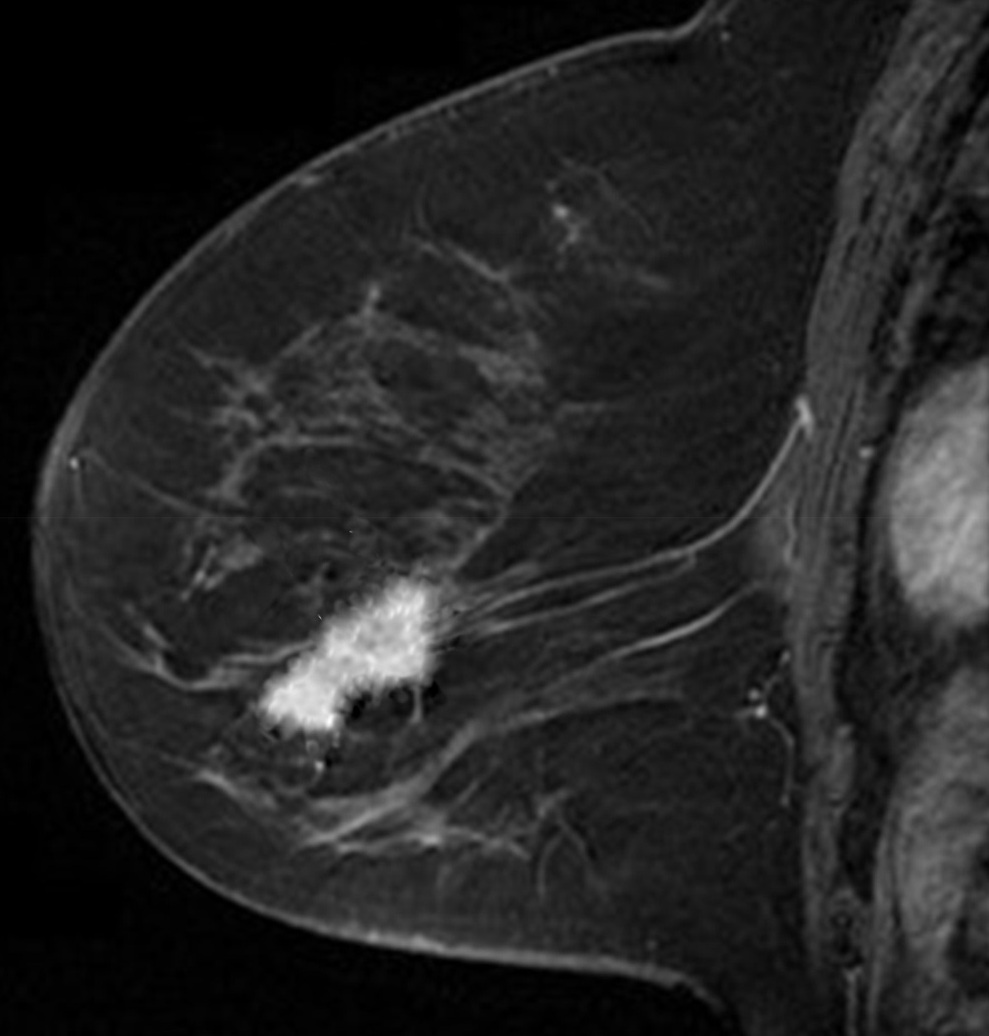

First we will use a Magnetic Resonance (MR) image of a female breast, taken from eby2008magnetic with permission from111www.slicer.org, to segment the tumor mass. On the top/right of Fig. 4, we see the first eigenfunction segmenting the tumor perfectly out of the breast image. Next, in the middle row of Fig. 4, we add to the image , of standard Gaussian noise, such that

where is i.i.d. Gaussian random variable with mean zero, variance equal to one and represents the noise level. Now, we compute the adaptive eigenspace of . Again, the first eigenfunction holds a nice segmentation of the tumor despite the additional noise. To demonstrate the quality of our approach, we consider the image but this time we destroy the boundaries of the tumor and change them by blurring (using an image manipulation program). The resulting image is shown on the bottom left of Fig. 4. On the bottom right of Fig. 4, we see the segmentation is accurate and captures the tumor and its blurred boundaries.

To reduce computational cost and get even more accurate results, we may create a Finite Element (FE) grid on the area of interest rather than on the image boundaries. For illustration, we consider the MR-images and shown on the top/left and bottom/left of Fig. 4, respectively. We automatically produce a mesh on the breast boundaries (see on the left of Fig. 5). The segmentation for and for is shown on the center and right of Fig. 5, respectively.